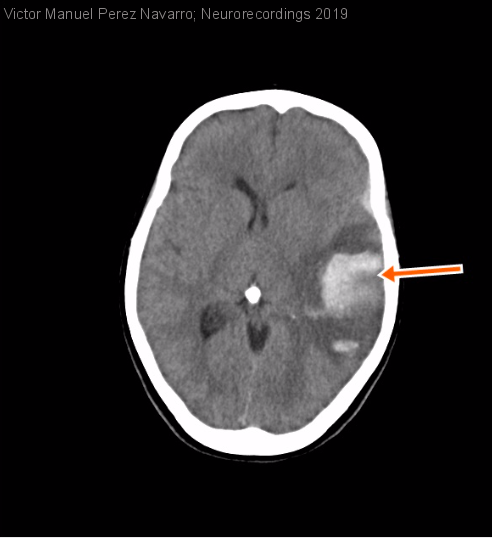

Mujer | 46 años

Diagnóstico final: trombosis de senos venosos

Paciente mujer de 46 años que consulta por cefalea y alteración del lenguaje. Entre sus antecedentes personales no refiere alergias ni otros antecedentes médico-quirúrgicos de interés. En tratamiento crónico con anticonceptivos hormonales orales.